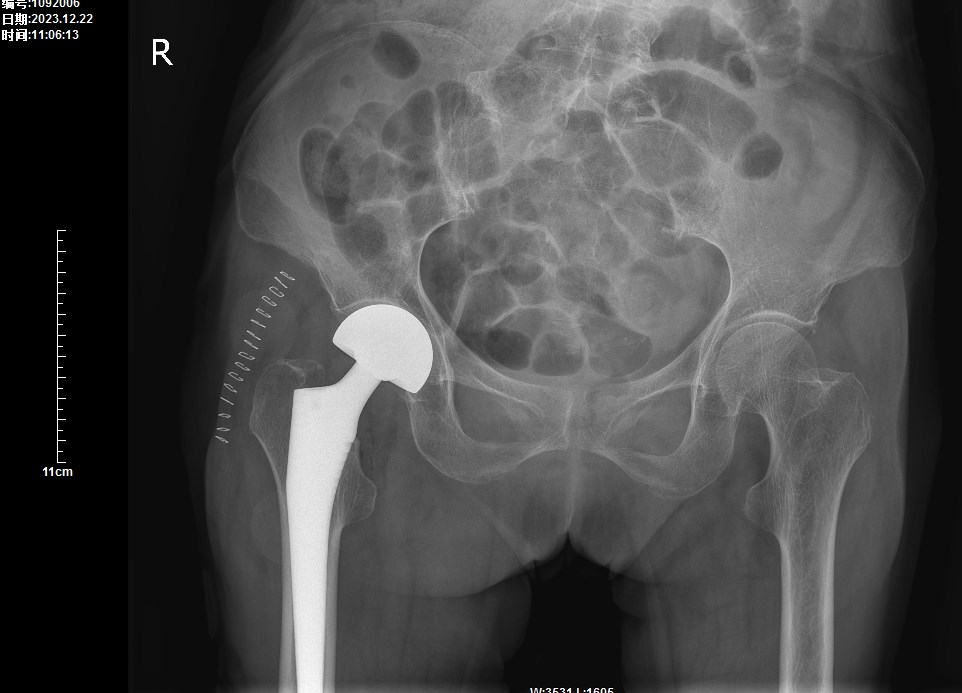

在了解到李奶奶的相关情况后,骨科医师团队组织呼吸与危重症医学科、麻醉科及心血管内科进行详细的术前评估。认为李奶奶手术和麻醉风险虽大,但并非手术禁忌。经过与患者及家属充分沟通,取得同意后,为李奶奶实施了:右侧人工股骨头置换术。

手术历时1小时,术后2天李奶奶便在助行器的保护下可下床行走,术后14天顺利拆线出院回家静养。

术后X片